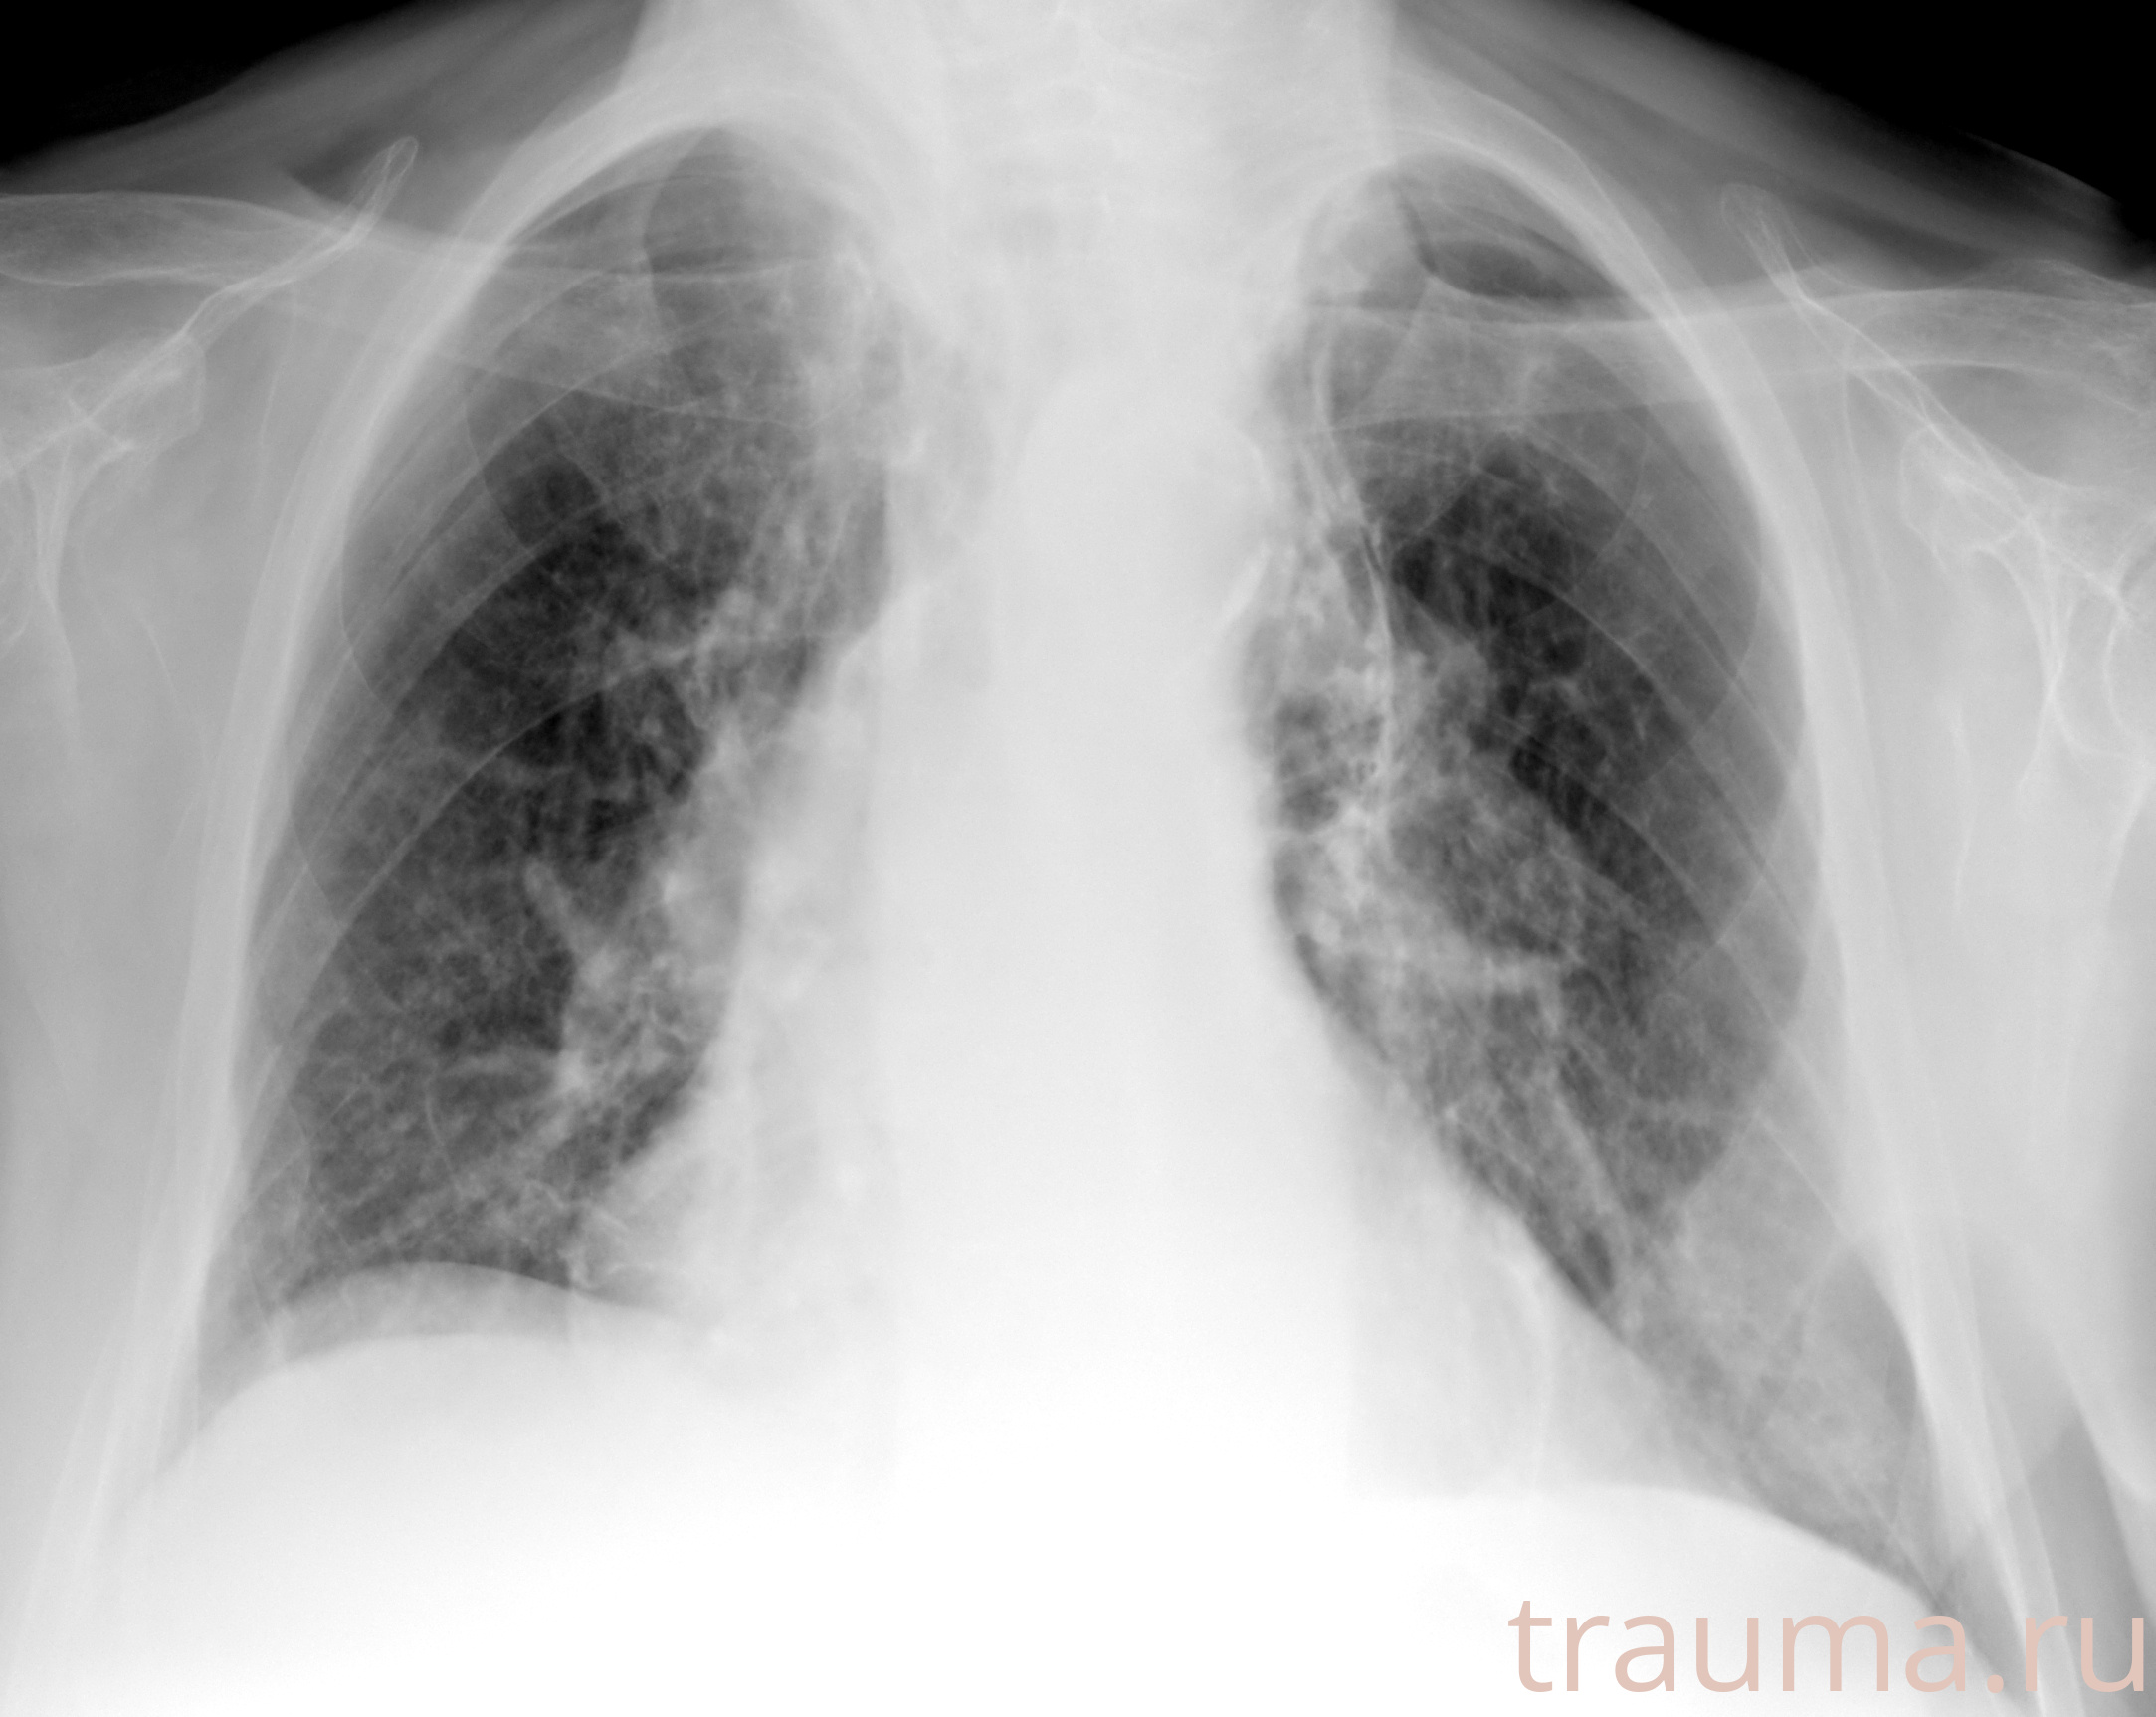

Рентгенограммы

Рентген на дому: по вашему адресу приезжает врач-рентгенолог, травматолог-ортопед с мобильным рентгеновским аппаратом, проводит диагностику травмы или заболевания, делает необходимые рентгенограммы, дает рекомендации по дальнейшему лечению. Получить качественные снимки в домашних условиях возможно благодаря уникальной методике, разработанной МосРентген Центром для института  Склифосовского

Яркость: 1   Контраст: 1   Инвертировать: 0 Увеличение: 1

Перетаскивайте мышь вверх/вниз для контраста, влево/право для яркости. Прокрутка колесом изменяет масштаб. Нажмите Сбросить для возврата к исходному изображению. При увеличении держите мышь в той области, которую хотите рассмотреть.